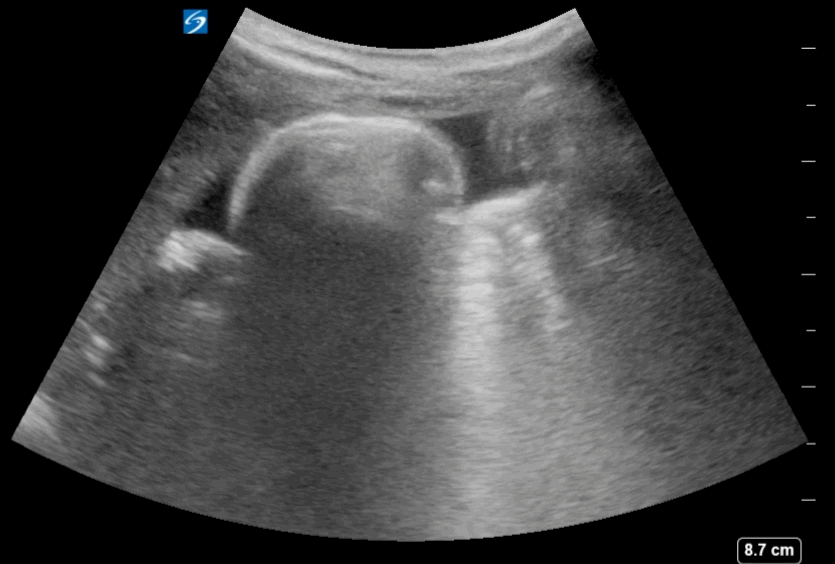

Free Fluid in between the Intestinal loops